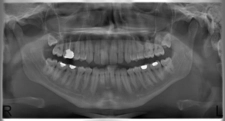

Bu belirtiler, lezyonun yerleşim yeri ve büyüklüğüne göre değişiklik gösterebilir. 4. Tanı YöntemleriYoğun içerikli kistik lezyonların tanısı, çeşitli görüntüleme yöntemleri ve biyopsi ile yapılabilir. Kullanılan başlıca tanı yöntemleri şunlardır:

Tanı Yöntemleri: Ultrasonografi ve manyetik rezonans görüntüleme (MRG) gibi tanı yöntemlerinin etkili olduğunu deneyimlemiş olmanız, bu süreçte ne kadar önemli bir yere sahip olduklarını gösteriyor. Bu yöntemler, lezyonların doğru bir şekilde değerlendirilmesi için kritik öneme sahiptir.